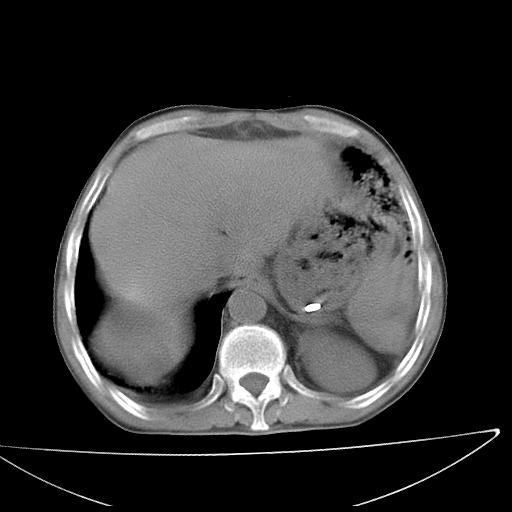

男  70岁,发烧咳嗽4天。盗汗,消瘦。无痰中带血丝,以前有肺tb病史,ct见,双肺tb,左侧胸廓塌陷,左胸膜肥厚粘连。纵隔移位,右侧胸腔积液,大家说说那个心影前左肺舌叶除了肺大炮还有炎症还是干酪性肺炎?有占位吗?我看纵隔淋巴结也大。

1)两肺继发性肺结核并左肺上叶肺不张,支气管扩张。2)双侧胸膜炎(胸膜增厚+少量胸腔积液)。

双肺继发性肺结核伴部分左肺毁损!

两肺继发性肺结核并感染,左肺上叶肺不张。建议ct增强。